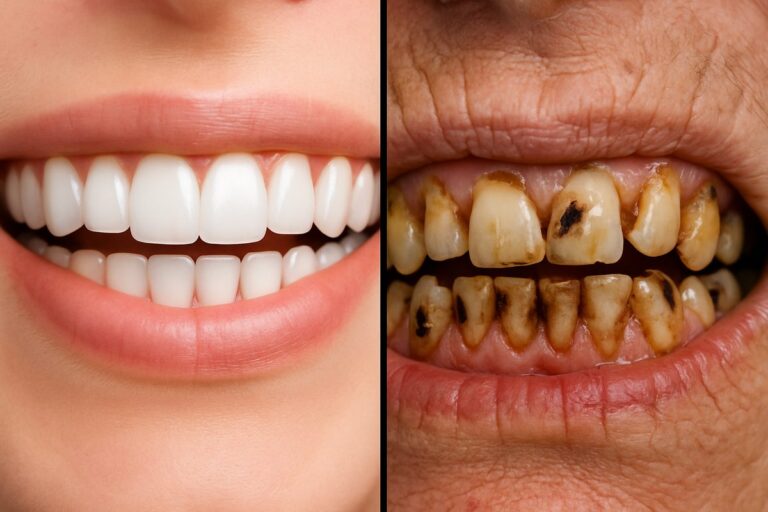

Understanding & Preventing Diseases Of Teeth Good teeth matter for comfort, eating, and your overall health. Diseases of teeth are problems that damage tooth structure